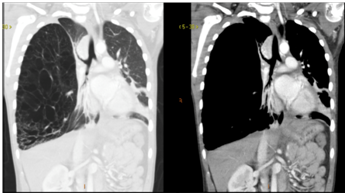

Figure 5 Gross pathology of right middle lobe.

Pediatric general surgery was consulted and was in agreement with highest suspicion of our differential diagnosis of type I congenital pulmonary airway malformation (CPAM). Given the patient was symptomatic with her suspected CPAM, outpatient surgical resection was recommended (lobectomy versus segmental resection, while pneumonectomy is considered in patients with extensive multilobar involvement) following resolution of the acute illness present at initial hospitalization. The patient returned two months post-discharge and underwent right thoracoscopy, thoracotomy with right middle lobe resection with right-sided chest tube placement postoperatively. Operative findings were significant for multiple adhesions from the right middle lobe to the pleura, consistent with chronic inflammation or prior infection, grossly distended right middle lobe which was emphysematous throughout. The patient had resolution of the right pneumothorax within a week of the operation.